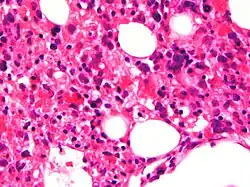

| Micrograph showing red blood cells within macrophages. H&E stain. | |